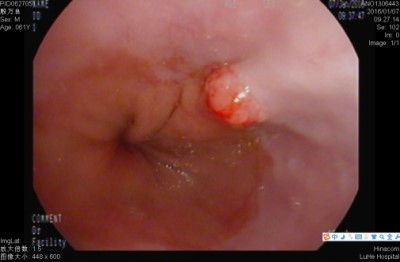

一、食管贲门癌

引起食管贲门癌的危险因素:(1)烟和酒:长期吸烟和饮酒与食管癌的发生有关。(2)食管的局部损伤:长期进食粗硬食物、热汤、烫粥、烫茶或辣椒之类刺激性食物(3)亚硝胺:亚硝胺类化合物是一种很强的致癌物,已知有十几种亚硝胺能引起动物的食管癌。(4)霉菌:已有研究发现10多种霉菌毒素能诱发动物不同器官的肿瘤。(5)营养和微量元素:膳食中缺乏维生素、蛋白质及必须脂肪酸。这些成份的缺乏,可以使食管黏膜上皮增生、间变、进一步引起癌变。(6)遗传易感性:临床流行病学研究发现,食管癌有一定的家族聚集性,不排除有遗传因素参与。

食管癌的早期信号:(1)噎食:就是咽食物时有阻力,咽食不畅,有堵塞感、或有异物感,呈渐进性加重,(2)吞咽困难:吞咽时胸骨后有轻度闷、胀不适感或隐痛感,常在饮水、喝酒或喝酸性饮料时,出现食管内持续性灼痛或刺痛。(3)吞咽异物感:吞咽时自觉食管内有异物,似饭粒或茶叶碎片黏附于食管上,咽之不下,吐之不出。以上三种症状的发生率占全部早期食管癌症状的80%以上,而吞咽不适的感觉占全部症状的30%以上。